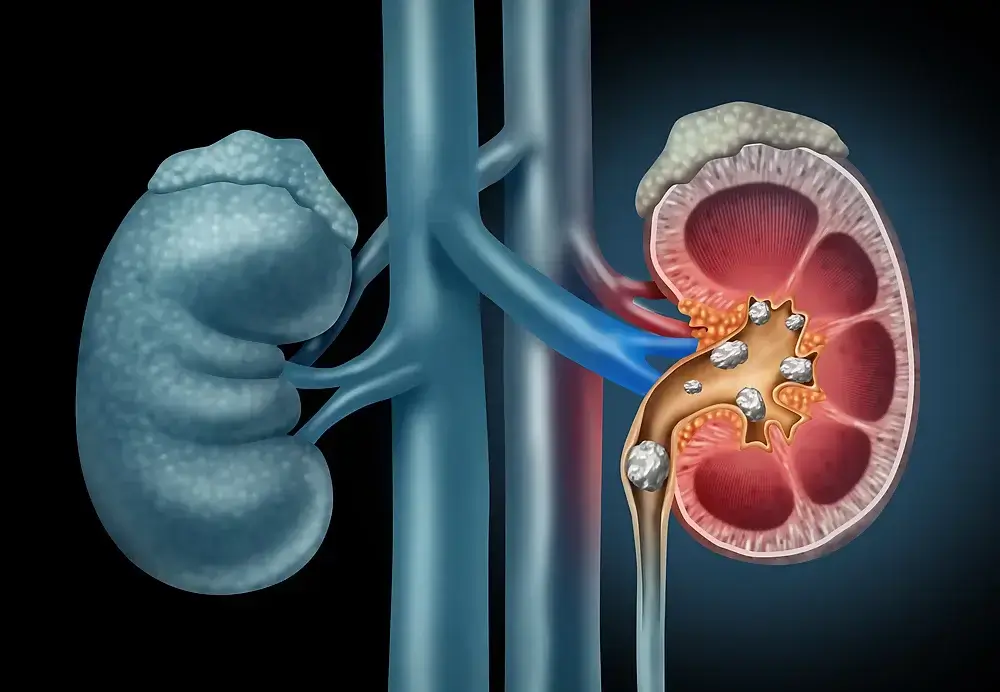

Kidney Stones

Kidney stones are small crystalline masses that can form in the kidneys. They are most common in people over the age of 50, but can also occur in younger adults.

A kidney stone is a solid, painless (and rarely painful) mineral deposit that forms in the urinary tract. Stones are usually formed of calcium or struvite, but may also be composed of other minerals such as oxalate, uric acid, cystine and phosphate.

Kidney stones can cause pain and difficulty urinating. They can also lead to complications such as infection, blood clots, and even death. If not addressed, stones can cause serious health problems.

The best way to prevent kidney stones is to have a healthy diet and drink plenty of water.